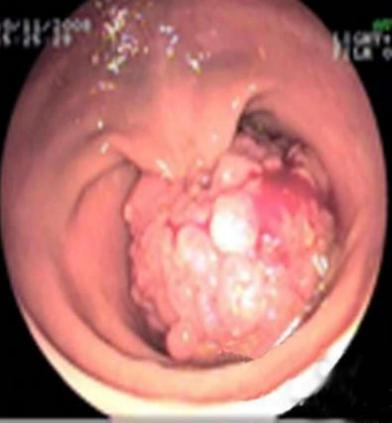

直肠癌可以摸到肿块质地较硬,表面高低不平或呈菜花样,有脓液、坏死组织及暗红色的血液,并感觉肠腔狭窄,指套上也染有暗红色血液。